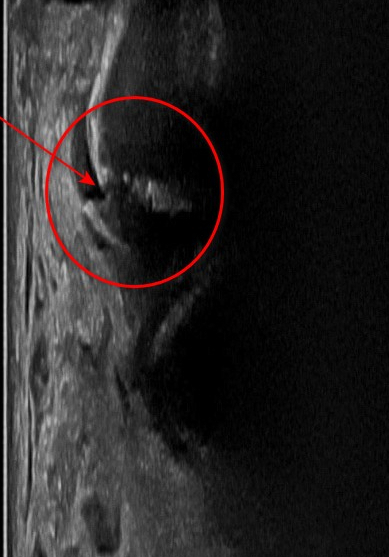

표준 경혈초음파와 달리

하나로 연결되어야 할

골 피질이 두개로 나눠져있고요.

초음파 빔이

뼈 내부로 들어갑니다.

골막 아래로

혈종이 보이고

눌렀을 때

평소 아팠던 통증이

그대로 나타납니다.